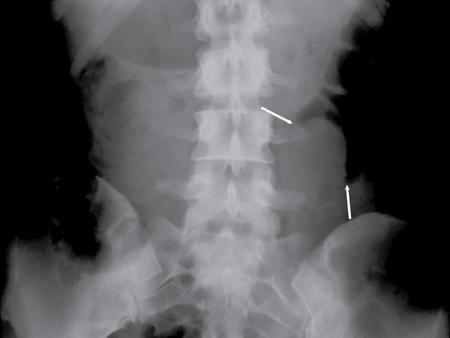

UNDERSTANDING THE ADULT ABDOMINAL RADIOGRAPH: TECHNIQUES AND INTERPRETATION Tanvi Modi Radiography of the abdomen is a common practice for the evaluation of abdominal organs. The anatomy and pathology of digestive, hepatobiliary and genitourinary systems can be assessed using radiographs, either as a stand-alone practice or as a primary imaging modality followed by contrast studies, ultrasound or cross-sectional imaging. In addition, abnormalities of the musculoskeletal or integumentary system can also be deduced on the basis of abdominal radiographs. This chapter intends to give an overview on the techniques and positioning in abdominal radiography as well as interpretation of normal and abnormal features. While superior imaging modalities such as ultrasound, computed tomography (CT), magnetic resonance imaging, capsule endoscopy and the likes have taken over abdominal imaging by and large, radiography still holds a pivotal role in certain situations and conditions, such as: The standard abdominal radiograph is taken in supine position and anteroposterior projection. This is also popularly known as the KUB (kidneys-ureters-bladder) radiograph. Previously, supine as well as erect radiographs were performed in all patients; however, this is not commonly done due to high-radiation dose. For all indications of abdominal radiography, including acute abdomen, supine radiographs are sufficient in terms of radiographic diagnosis, with the exception of perforation for which an erect chest or lateral decubitus radiograph can be performed if there is clinical suspicion. Patient should lie supine on the imaging table with median sagittal plane at right angles to the table and coincident with the midline of the table (Fig. 7.1.1.1). The body is divided into equal right and left halves by the median sagittal which passes through the sagittal suture of the skull. Pelvis should be adjusted so that the anterior superior iliac spines are equidistant from the table top. Gonadal shields, in the case of male patients, should be placed with the upper edge of the shield at the level of pubic symphysis. Although rarely used for female patients, these should be positioned between the anterior superior iliac spines and the pubic symphysis. The centre point of the image receptor should be approximately located at a point 1 cm below the line joining the iliac crests. The X-ray beam should be in a vertical direction, perpendicular to the table top and image receptor at the centre point. Collimation should be such that the soft tissue and subcutaneous region along lateral aspects of the abdominal cavity should be covered within the image. Also, the superior extent involving diaphragm and inferior extent involving the inferior pubic rami is important to look for any lower chest pathologies or any inguinal hernia. 35 × 43 cm (14 × 17 inches) in portrait orientation. On an average, abdominal radiograph exposes a patient to a dose of approximately 1.5 mSv, which is equivalent to 75 chest radiographs or 1/6th dose of a standard CT of the abdomen. The entrance skin dose is approximated to be 4 mGy. At such an effective dose, the additional lifetime risk of fatal cancer is 1 in 30,000. The exposure time is kept short. Patient is asked to exhale completely and hold their breath, with exposure taken at this point of full expiration to ensure imaging of abdominal organs in their natural positions. Modifications of this technique can be made depending on patient habitus and clinical condition. Kilovoltage peak (kVp) should be set to allow adequate visualization of abdominal soft tissue structures as well as semiopaque renal and biliary calculi. Average kVp is set at 70–85 kV. 102 cm (40 inches) Grids are commonly used to reduce scatter radiation. Placement of side marker on the image receptor at the time of radiographic exposure is essential. Bowel pattern depiction should be such that there is minimal lack of sharpness. Standard guidelines for abdominal radiography dictate that the radiograph should extend from the diaphragm up to the level of inferior pubic rami and must include the lateral abdominal wall musculature. The abdomen is divided into four quadrants on the basis of two perpendicular lines (Fig. 7.1.1.7). The vertical line passes through the mid sagittal plane and crosses the umbilicus and symphysis pubis. The horizontal line is a transverse line across the umbilicus at 90 degrees to the vertical line and is situated at the level of L4–L5 intervertebral disc. The quadrants are as follows: Another division system is dividing the abdominopelvic cavity into nine regions using two vertical and two horizontal planes (Fig. 7.1.1.8). The vertical planes, also known as the right and left lateral planes, are parallel to the midsagittal plane between midline and anterosuperior iliac spines on either side. Of the two horizontal planes, the upper transpyloric plane is at the level of lower border of L1 and the lower transtubercular plane is at the level of L5. The nine regions are: On a standard radiograph, the exposure should be such that the stomach, bowel loops, outlines of liver, spleen, kidneys, psoas muscles should be well identified. Also, lumbar transverse processes should be seen. Arch of the pubic symphysis should be visible to evaluate bladder region. A well-centred film without rotation will demonstrate bilaterally symmetrical lower ribs, iliac wings, ischial spines and obturator foramina. Different structures seen on an abdominal radiograph can be classified into five basic densities: Identification of different structures depends on the relative degree of contrast between their densities. The demarcation is clearer in chest and is diminished in abdomen due to relative similar soft tissue density of various structures. On a normal radiograph, relatively large amounts of gas in stomach and colon with minimal small bowel gas can be seen. Further, colonic gas can vary from negligible to extensive, mimicking obstruction pattern; however, usually the gas is enough to delineate colonic haustral pattern. Faecal matter gives a mottled appearance to colonic gas. Short-air fluid levels on an erect radiograph may be seen even in normal cases. The normal appearance of small bowel loops on an abdominal radiograph follows the rule of threes: Stomach is seen in the left upper quadrant and is visualized when distended with air. It is commonly seen extending from T11 to L2 level. Common feature identifying the stomach is the fundal gas which is usually seen as an air fluid level within the gastric lumen. Small bowel loops are distributed to the centre of the abdominal cavity and large bowel loops are peripheral. Duodenum is predominantly situated in right upper quadrant. It extends to left upper quadrant in the region of duodenojejunal flexure. Jejunum occupies the left upper and lower quadrants and is easily identified due to the presence of thick, numerous, closely spaced valvulae conniventes (Fig. 7.1.1.9A). The ileum occupies both lower quadrants and extends into right upper quadrant. Ileum has few and less prominent valvulae as compared to jejunum (Fig. 7.1.1.9B). Ascending and descending colon are retroperitoneal and have relatively fixed positions along lateral aspect of the abdominal cavity on either side. Transverse and sigmoid colon, on the other hand, may have a variable position due to their mobility along mesocolon and redundant pattern. These can be identified with confidence on account of haustrations and faecal matter (Fig. 7.1.1.10). Haustrations are usually well seen in ascending and transverse colon and poorly delineated beyond splenic flexure. Caecum is in the right lower quadrant, though it may be mobile or pulled up. Rectal gas is usually seen in the midline at the level of pelvis and its presence rules out large bowel obstruction. All these positions may vary due to anatomical conditions such as malrotation or pathological conditions, for example volvulus. Liver, spleen and renal outlines cannot be completely traced with precision due to the overlap by bowel loops. On a frontal projection, the liver appears as a triangular structure occupying right and left hypochondrium and epigastric region. Occasionally, the right lobe may be seen extending lower than the right renal shadow. This is a normal variant known as Reidel’s lobe. Gall bladder is situated in the posterior and inferior region of the liver and any pathology of the gall bladder should be looked for in this region. On a lateral radiograph, the gall bladder is anterior to the midcoronal plane. This helps in distinguishing gall bladder calculi from renal calculi, which will be more posteriorly situated. Spleen is seen in left upper quadrant/left hypochondrium, flushed to left lower ribs and left hemidiaphragm. Pancreas is present in the epigastric region (right and left upper quadrants) and is usually not identified in the absence of a pathology. The kidneys are bean-shaped retroperitoneal organs which are seen on either side of the vertebral column and lateral to psoas muscles. Due to the presence of liver on the right side, this kidney is slightly lower in position as compared to its contralateral counterpart. The visualization of kidneys on radiographs is facilitated by the surrounding fatty capsule. Kidneys lie between T11–12 and L2 level, with left kidney 1 cm higher than the right. Psoas muscle shadow can be normally seen along lateral aspect of lumbar spine bilaterally and is mildly concave (Fig. 7.1.1.11). Abdominal wall muscles are not routinely assessed on radiography; however, inclusion of lateral abdominal wall (muscles as well as subcutaneous plane) is a must while performing radiography. The flank stripe or the properitoneal fat stripe is a fat density linear concavity seen along lateral abdominal wall (Fig. 7.1.1.11). It is bound by the paracolic gutters and air-filled ascending and descending colon. All the solid organs in the abdomen are identified due to the fat density outlining them. Distortion of these fat lines helps in identifying organomegaly or focal mass lesions. The dome of urinary bladder is outlined by fat, which aids in differentiating its density from other soft tissue structures of the pelvis. Not all calcifications seen on abdominal radiograph are abnormal. Some may depict age-related changes such as vascular calcifications involving abdominal aorta, pelvic vessels, splenic artery in the region of left upper quadrant. Within the pelvis, phleboliths may be seen and mistaken for urinary calculi. Assessment of lumbosacral spine, iliac bones and femoral heads can be made on the basis of plain radiography. Degenerative changes may be commonly seen. Lower ribs can also be evaluated for pathologies. Dilated small bowel loops with rounded soft tissue density in midline over umbilical region suggests obstruction secondary to umbilical hernia. Pneumoperitoneum must be looked for in all cases of acute abdomen. While erect chest and left lateral decubitus radiographs can detect even 1 mL of free air, there are multiple signs on supine radiograph to suggest this diagnosis, for example Rigler’s sign, falciform ligament sign, football sign (Figs. 7.1.1.24 and 7.1.1.25). Retroperitoneal perforation may demonstrate air outlining psoas muscles and retroperitoneal organs. Small amount of free air may persist in the abdominal cavity up to 3 weeks after surgery, although it usually resolves within a week. Clinical history is important in such cases. Air foci within the bowel wall may represent bowel ischaemia/strangulation. Linear gas patterns in right hypochondrium may be due to two causes, that is pneumobilia and pneumoporta. The former can be seen normally postbiliary surgery, sphincterotomy, ERCP or in the case of abnormal fistulous communication between bowel and biliary tree (Fig. 7.1.1.26A). Pneumoporta (Fig. 7.1.1.26B) is a red flag and warrants further investigation to look for conditions such as mesenteric ischaemia and toxic megacolon. Pneumobilia is more centrally located whereas air shadows in pneumoporta are seen reaching up to periphery of liver. Air foci over renal shadows (Fig. 7.1.1.27), gall bladder or pancreas, in the absence of recent procedural history, suggest fulminant infection and mandate urgent intervention. Central midline calcific foci between T9 and T12 vertebrae can be attributed to calcific pancreatitis (Fig. 7.1.1.28). In the left upper quadrant, areas of calcification seen involving a shrunken spleen may be seen in autosplenectomy. In right upper quadrant, calcified gall stones may be seen. These tend to be small, multiple, uniformly circumscribed and ring-like in appearance with central translucency (Fig. 7.1.1.29A). Mercedes Benz sign, a triradiate pattern of gas lucency, is associated with gallstones. In contrast, renal calculi are more commonly solitary, irregular, of homogenous density, conform to renal calyceal or pelvic outline (Fig. 7.1.1.29B) and are sometimes of staghorn configuration. On lateral view, the gall stones are more anteriorly located as compared to renal calculi, which may be partly superimposed on lumbar vertebrae. Ureteric calculi tend to overlap bony structures such as lumbar transverse processes (Fig. 7.1.1.29B) or sacroiliac joints. Extensive or patchy, curvilinear calcification of gall bladder wall is known as porcelain gall bladder which is often associated with malignant transformation. Calcification involving adrenal glands may be secondary to infection or haematoma, or a congenital condition known as Wolman’s disease where there is bilateral involvement. Discontinuous discrete midline tram track calcification in the abdomen may indicate atherosclerotic changes in abdominal aorta and branch vessels. However, when the calcification is in a globular pattern and seen below the level of L2 vertebra, aortic aneurysm should be suspected (Fig. 7.1.1.30). Appendicoliths, though not commonly seen, may sometimes be detected in right iliac region. Pelvic calcifications: vesical calculi, distal ureteric or vesicoureteric junction calculi, calcified fibroids, ovarian dermoid with tooth-like calcifications (Fig. 7.1.1.31) may be the cause of abdominal pain and should be diligently looked for. Vesical calculi are usually more large and central in location whereas calcification due to fibroids may be more lateral. Schistosomiasis is another cause of bladder wall calcification, as is calcification of bladder tumours. Phleboliths tend to be bilaterally symmetrical, with a lucent centre unlike ureteric calculi. While it is believed that phleboliths are located below the level of ischial spines and ureteric calculi above, this is not always true and should be confirmed with CT. Fluid may collect adjacent to properitoneal fat line, forming a linear soft tissue density separating the fat line from the ascending or descending colon. Hellmer’s sign demonstrates medial displacement of lateral edge of liver (hepatic angle), due to fluid collection or ascites. Gross ascites may appear as generalized abdominal haziness or diffuse increased density of pelvis. Abscesses can involve any solid organ and in such cases may be difficult to demonstrate on plain radiography alone. Enlargement of organ or faint gas densities within can be suggestive of the same. In the case of peritoneal abscess, mottled density due to air, fluid and necrotic contents point towards this diagnosis, especially in right iliac fossa in association with appendicitis. Retroperitoneal abscess, similar to any retroperitoneal mass, may cause displacement of retroperitoneal structures (Fig. 7.1.1.32). Subdiaphragmatic abscesses may show concomitant ipsilateral pleural effusion (Fig. 7.1.1.33). These should be differentiated from Chilaiditi syndrome. Fluid and soft tissue lesions present with the same density on radiographs. While it is difficult to characterize the lesion and organ of origin, clues for the same can be provided by organomegaly (Fig. 7.1.1.34), distortion of fat surrounding solid organs, displacement of bowel loops or solid organs. For example, a retroperitoneal lesion may cause anterior or inferior displacement of kidney, a pelvic mass may cause upward displacement of small bowel loops. Different densities such as fat or calcification may help in identifying organ of origin (e.g. fat and tooth densities seen in ovarian dermoid). Convexity of margins of psoas muscle on an abdominal radiograph can be due to haematoma, abscess or intramuscular tumour. Radiographs are performed for the initial diagnosis of foreign body in the abdomen including type, number of foreign bodies, location, size and shape (Fig. 7.1.1.35). Radiolucent foreign bodies such as wood, plastic, chicken bones will not be easily identified on radiography. Low kVp (65–70 kVp) can increase contrast and help identify these objects. In addition to an abdominal radiograph, chest radiography is also performed to exclude aspiration or oesophageal location of foreign body. Ingested or introduced foreign bodies may cause complications such as obstruction, perforation, fistula formation and sepsis. Hence, once their presence is confirmed, follow up radiography must be performed until they are eliminated. One must look for fractures/dislocation injuries involving the vertebrae or pelvic bones, especially after history of trauma. Lucent expansile lesions or sclerotic bony deposits which represent neoplasms, absent pedicle sign in cases of metastasis, metabolic bony changes such as rugger jersey appearance, Paget’s disease, arthropathies such as ankylosing spondylitis with bamboo spine appearance and sacroiliitis (Fig. 7.1.1.36) are some of the conditions which may be diagnosed based on an abdominal radiograph. Overlap of bowel loops over iliac blades may lead to a misdiagnosis of lucent lesions and should be evaluated with caution. Basal pneumonia may be the cause of acute abdominal pain and should be looked for in abdominal radiography. Similarly, pleural effusion, pericardial effusion, calcified pleural plaques, achalasia, interstitial fibrosis are few other findings that can be seen in lower chest on an abdominal radiograph. Basilar atelectasis can give a deceptive appearance of pneumoperitoneum (Fig. 7.1.1.37). Surgical clips, commonly in right hypochondrium after cholecystectomy, drainage tubes, ventriculoperitoneal shunts, femoral line catheters, IVC filters, stents (vascular, renal, biliary) (Fig. 7.1.1.38), stoma bags, contraceptive devices are some structures that may be seen in an abdominal radiograph. Correct knowledge of patient history and normal locations of these structures prevents misdiagnosis. Certain artefacts may be projected upon the radiograph due to surface structures such as trouser buttons, body piercing, sequins over clothing and should not be considered as a pathology. Multiple skin surface nodules in cases of neurofibromatosis, soft tissue focal swellings, such as abscesses, lipomas, haematomas, desmoid tumours and malignant lesions may be incidentally seen on radiography. These can be further evaluated using ultrasound or CT. Subcutaneous emphysema is another finding that may be seen in lower abdominal wall secondary to retroperitoneal perforation or diffusely along abdominal wall in the case of bowel perforation (Fig. 7.1.1.39). Foreign bodies such as bullets and pins may be seen lodged in abdominal wall. A systematic approach to abdominal radiographs is important for accurate diagnosis as follows: Despite the development of newer techniques for imaging of the abdomen, plain radiography still holds an important place in the initial assessment of acute abdomen. Positive and negative findings on an abdominal radiograph can direct further investigation. Ideal positioning, recognition of normal appearances and keen scrutiny for pathologies is a sine qua non for radiologists reading a plain film of the abdomen. OESOPHAGOGRAM Padma V. Badhe, Vikram Reddy, Sultan Moinuddin Shaukatali, Zillani Alam, Ravi Varma, Abhishek Bairy, Dasari Ravikiran, Revati Tekwani, Soniya Patankar, Megha Nair, Gautham Shankar Oesophagogram is the process of obtaining radiological images and simultaneous motion recording to evaluate function and disorders of pharynx, oesophagus and proximal stomach. Oesophagogram is usually done primarily to evaluate dysphagia. Some of the common indications are oesophageal motility disorders, strictures, gastro-oesophageal reflux disease (GERD) and suspected masses. It can also be used to detect uncommon anomalies like vascular rings/slings and aberrant anatomy. It also helps to evaluate further in cases where there is inability to pass upper GI scope. Double-contrast oesophagogram is mainly indicated in early mucosal disease like erosion, polyp, infection and tumours. If a motility disorder is suspected, dynamic technique (e.g. videofluoroscopy) is used for dysphagia or aspirations in cases of stroke, neuromuscular disorders, post head and neck surgery or radiation. Barium oesophagogram is contraindicated in suspected cases of perforation and tracheoesophageal fistula, aspiration, rarely if there is hypersensitivity to barium suspensions. It is also contraindicated in suspected oesophageal perforation where a water-soluble contrast agent is more suitable. However, ionic water-soluble contrast agent is better avoided in cases of aspiration or fistula with airway. The contrast examination of the pharynx is dangerous in cases of acute epiglottitis and must be ruled out on plain radiograph. An 80% w/v barium suspension is used in full column views. However, 200%–250% w/v barium suspensions is usually required for mucosal relief films. The barium sulphate mixture is fed to the patient either by spoon, by glass, or through a drinking straw, depending on its consistency. In videofluoroscopy, the pharyngeal phase of swallowing is usually safer with barium pudding than with thick barium and safer with thick barium than with thin barium. However, if the major abnormality is poor pharyngeal contraction leading to stasis in the piriform sinus (and epiglottic tilt is normal), a thin liquid is safer. Epiglottic motility is better assessed with thin barium because thick barium often obscures the epiglottic tip. Fluoroscopic equipment capable of cine fluoroscopy and capability for rapid sequence spot images (high frame rate) is needed for this examination, Barium suspension, straw, glass, Lead apron and radiation protective equipment. The patients are instructed to fast after midnight before the day of the examination. The pharynx should be made as dry as possible during the examination as high-density barium adheres to dry pharyngeal mucosa. Activities like smoking, chewing gum and lozenges must be abstained before the procedure as they impair barium coating by increasing the salivary secretion. Regular oral medications must be taken with sips of water; however, insulin must be skipped on the morning of examination. The major principles of a good oesophagogram includes mucosal coating, distension and projection. A routine oesophagogram consists of screening of the oral, pharyngeal and oesophageal phases of swallowing, single and double-contrast examination of pharynx, single contrast, double-contrast and mucosal relief views of the oesophagus. In cases of dysphagia, the examination is tailored depending on whether the symptoms are either pharyngeal or oesophageal and initial fluoroscopic findings. If patients’ symptoms are suggestive of oral or pharyngeal disorder then pharynx is evaluated first. Similarly, if patient is suspected to have thoracic oesophageal disease then, double-contrast examination of the oesophagus is performed before the pharyngeal evaluation. During an oesophagogram the positioning of the patient varies according to the type of examination (Table 7.1.2.1).